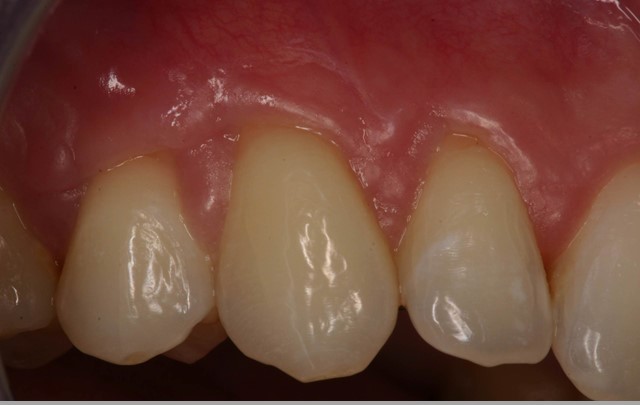

05/06 - Clinical situation 3 months post-operative. Significant coverage of the roots and increased thickness of the marginal tissue.Multiple gingival recessions treated with the modified coronally advanced flap in conjunction with mucoderm® - Prof. Dr. Dr. A. Kasaj